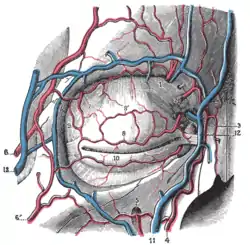

Diagram showing the origins of the main branches of the carotid arteries. Bloodvessels of the eyelids, front view.

Bloodvessels of the eyelids, front view.